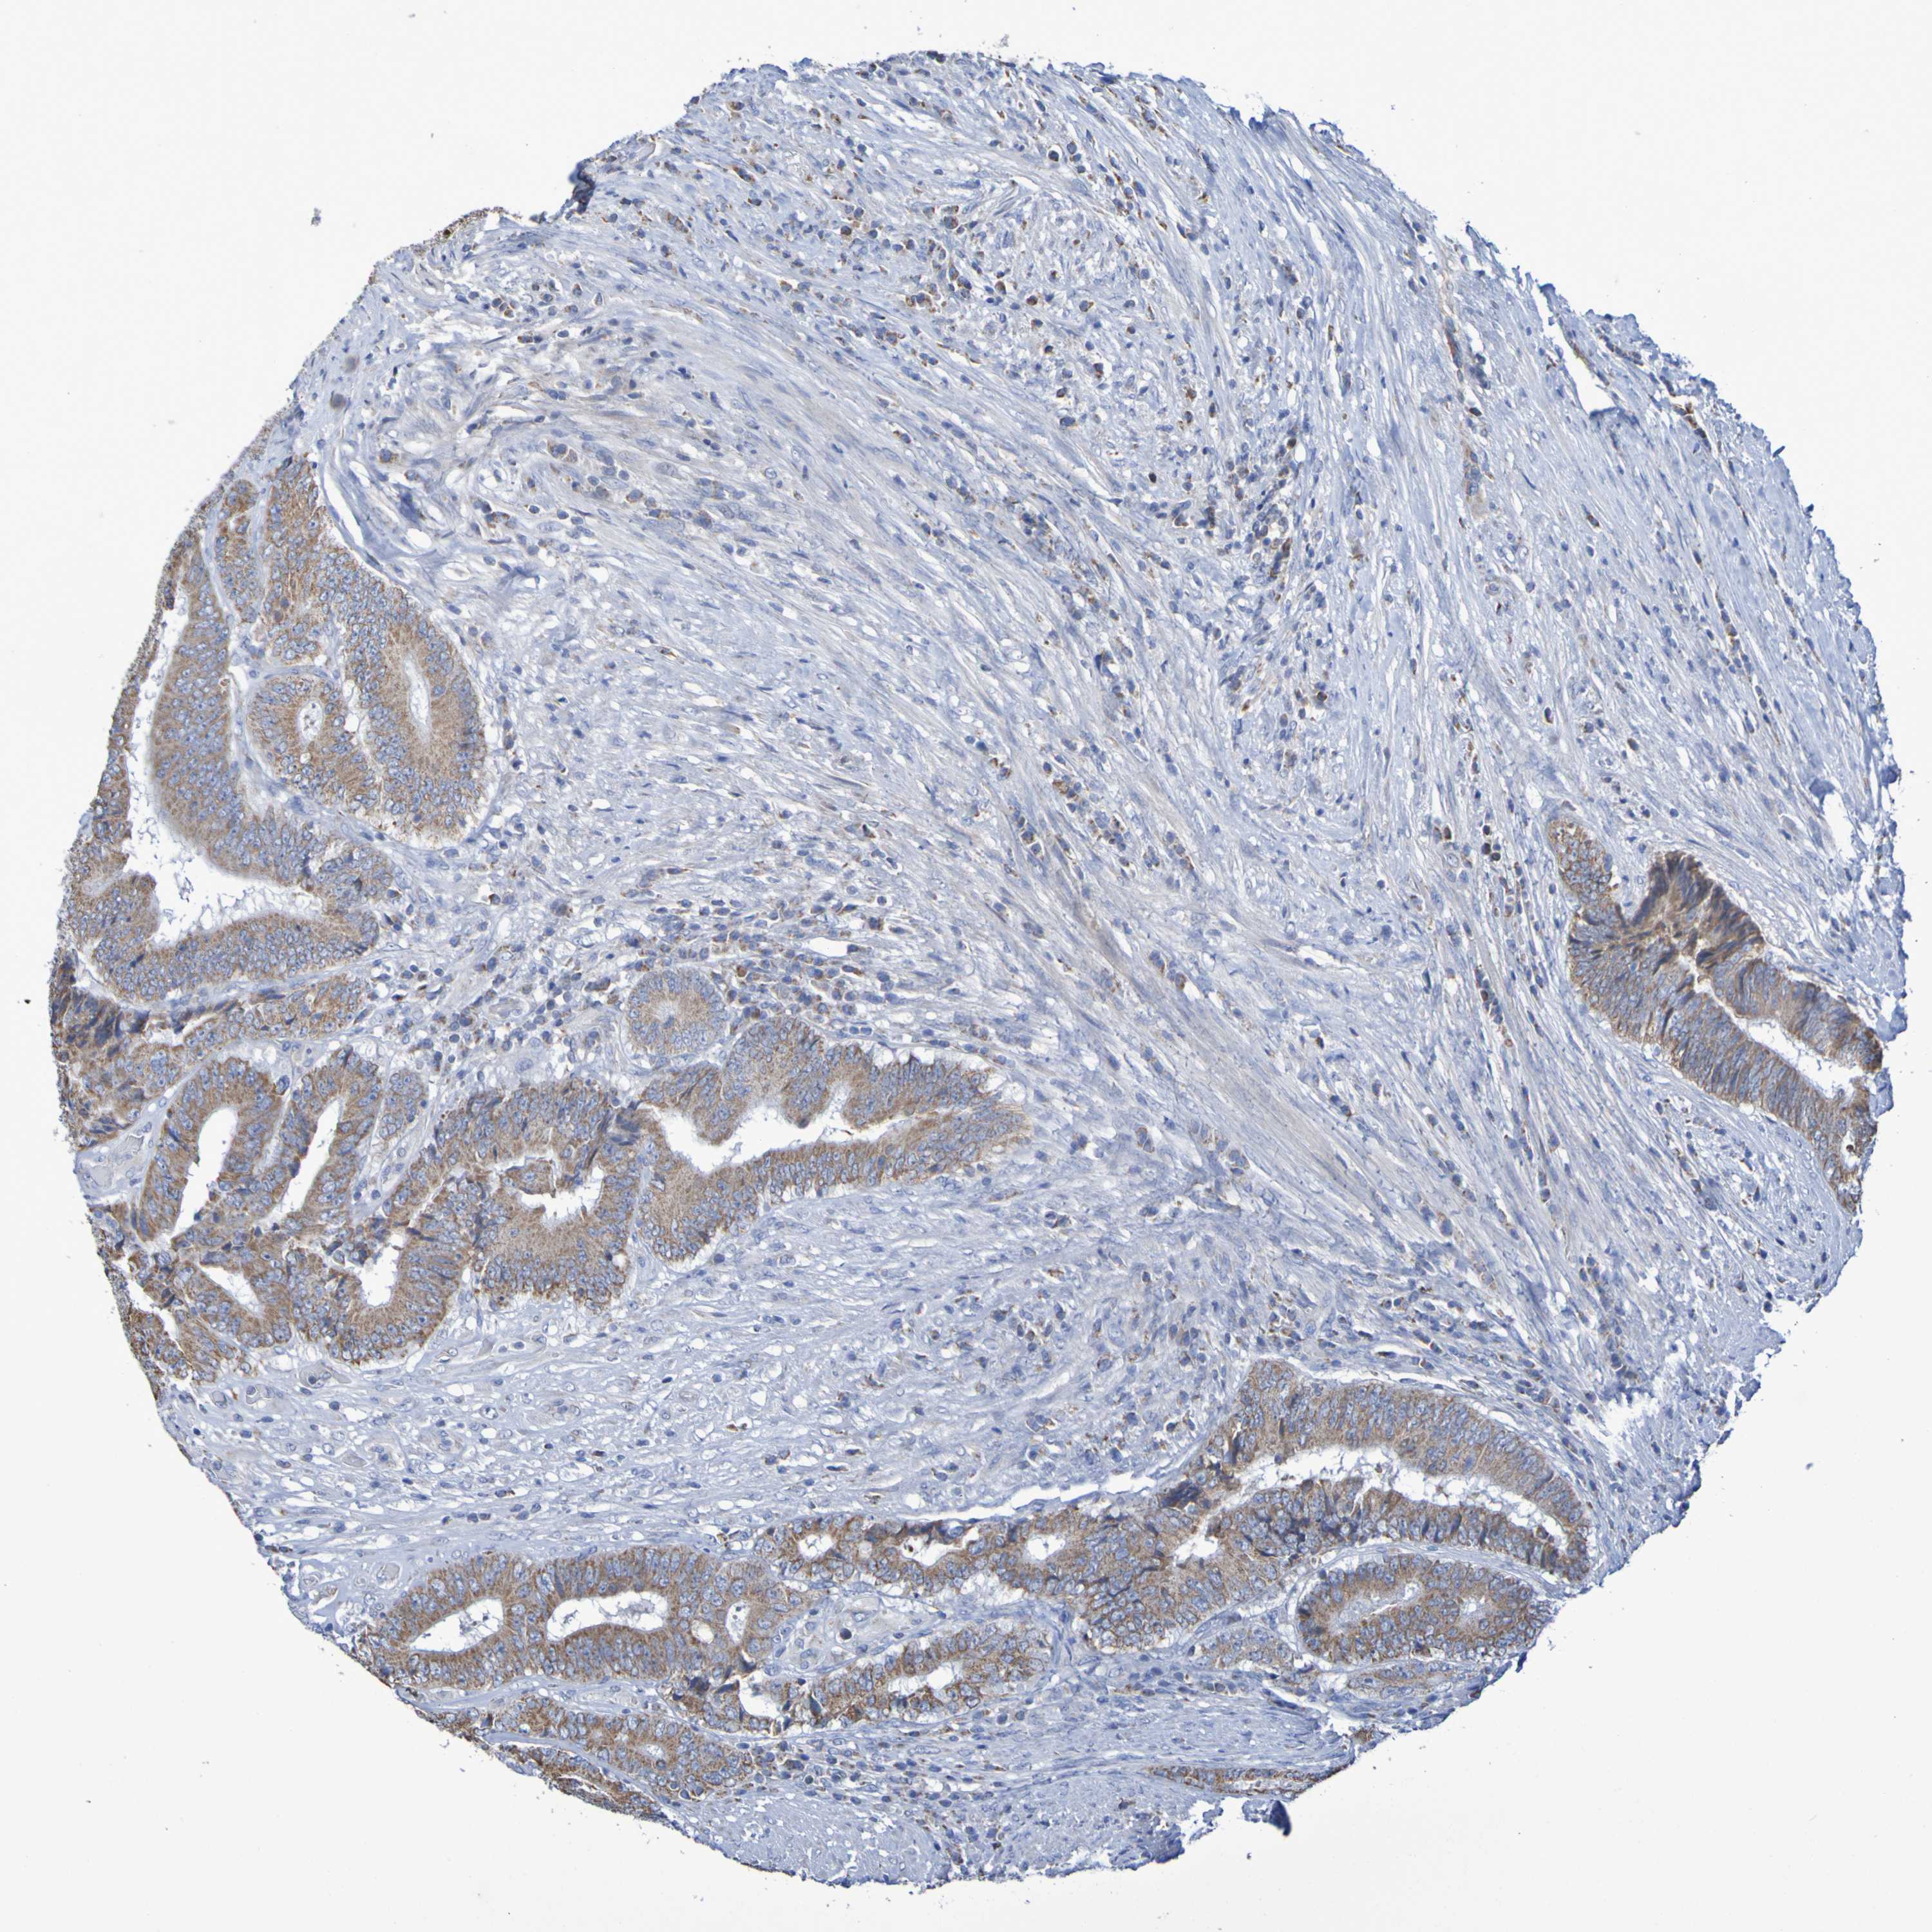

CANCER COLORECTAL CANCER Show tissue menu

Colorectal cancer

Human cancer

Colon adenocarcinoma